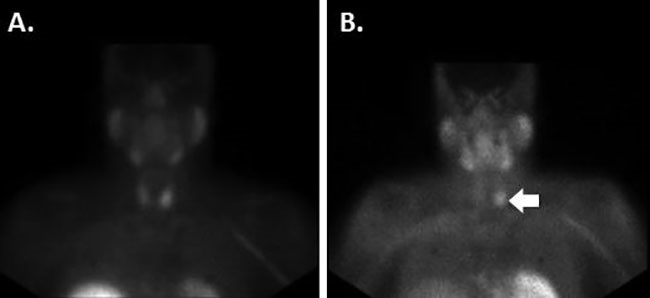

The patient was diagnosed with hypercalcemic crisis in the setting of PHPT, and admitted to the hospital for further management. Per the report, his clinical examination was normal, without evidence of palpable, firm or fixed cervical mass, or cervical lymphadenopathy. He received fluid resuscitation, intravenous bisphosphonate treatment, and calcitonin to treat his hypercalcemia. Loop diuretics were not administered given his acute renal insufficiency. He was noted to have mild hypokalemia and hypomagnesemia, which responded well to oral supplementation. A 24-hour urine collection demonstrated elevated calcium excretion at 614 mg (normal 100–321 mg per 24 hours). At the end of a four-day admission, calcium levels had decreased to 11.1 mg/dL, creatinine had decreased to 1.9 mg/dL, serum transaminitis had resolved, and the patient’s symptoms of fatigue had markedly improved. A DEXA scan performed during this hospitalization showed normal bone density. A neck ultrasound demonstrated a 2.3 cm nodule inferior to the left thyroid lobe, consistent with a parathyroid adenoma, without evidence of local invasion of the thyroid or other adjacent structures. A technetium-99m sestamibi scan showed focal uptake in the left lower neck (Figure 1), co-localizing with the lesion noted on ultrasound.

Figure 1: Anterior-posterior views of pre-operative technetium-99 sestamibi scan at 15 minutes (A.) and 2 hours (B.) after technetium administration, demonstrating marked uptake in the left lower neck (white arrow).